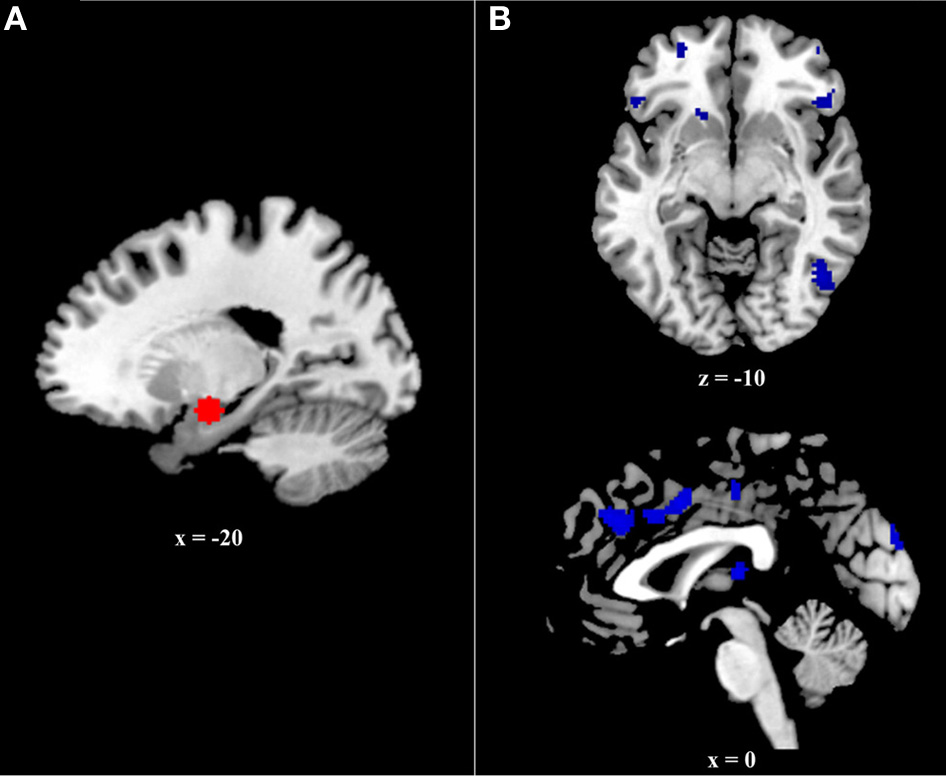

The current study examined connectivity between the amygdala and prefrontal regions during successful retrieval of positive, negative, and neutral events, utilizing the generalized psychophysiological interactions (gPPI; http://brainmap.wisc.edu/PPI; McLaren et al., 2012) toolbox in SPM8. The gPPI toolbox, which is configured to automatically accommodate multiple task conditions in the same PPI model, compares functional connectivity to a single seed region across tasks. Due to an a priori interest in connectivity with the amygdala, it was selected as our seed region. To identify the voxel within the amygdala showing the greatest effect of memory (i.e., greatest BOLD response to Hits>CRs), we ran an omnibus contrast at the group level that identified regions associated with retrieval (Hits>Correct Rejections) of all events (positive, negative, and neutral), controlling for age. The peak voxel within the amygdala (−20, −8, −16) from this group contrast, was used to create volumes of interest (VOIs) for each subject. Specifically, for each subject, a VOI was generated by creating a 6 mm sphere around this voxel (Figure 2A). Within each subject, the gPPI toolbox was used to estimate functional connectivity across the entire brain with this 6 mm VOI in the six memory conditions (i.e., Positive hits, positive CRs, negative hits, negative CRs, neutral hits, and neutral CRs) and to calculate the three contrasts of interest (i.e., Positive Hits>CRs, Negative Hits>CRs, and Neutral Hits>CRs).

Figure 2

(A) Six millimeter sphere used as the volume of interest (VOI) for psychophysiological analysis. The center of this VOI (−20, −8, −16) was selected via an omnibus contrast that identified regions associated with retrieval (Hits > Correct Rejections) of all events (positive, negative, and neutral), controlling for age. VOIs were created and defined functionally at the single-subject level. (B) Regions exhibiting greater age effects on the relation between functional and structural connectivity during positive event retrieval relative to negative event retrieval.